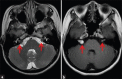

Schwannomas are benign soft-tissue tumors that arise from peripheral nerve sheaths throughout the body and are commonly encountered in patients with neurofibromatosis Type 2. The vast majority of schwannomas are benign, with rare cases of malignant transformation reported. In this pictorial review, we discuss the magnetic resonance imaging (MRI) appearance of schwannomas by demonstrating a collection of tumors from different parts of the body that exhibit similar MRI characteristics. We review strategies to distinguish schwannomas from malignant soft-tissue tumors while exploring the anatomic and histologic origins of these tumors to discuss how this correlates with their imaging findings. Familiarity with the MRI appearance of schwannomas can help aid in the differential diagnosis of soft-tissue masses, especially in unexpected locations.